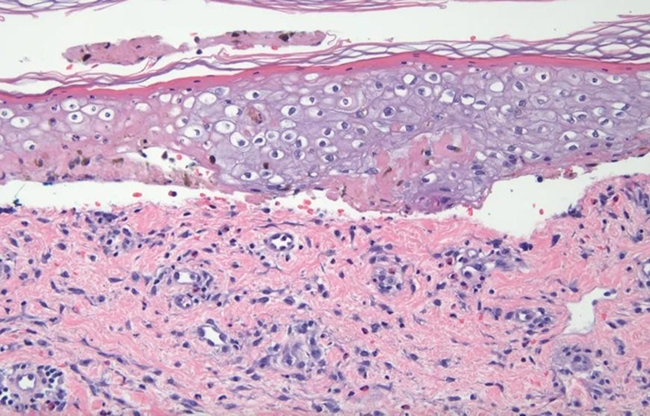

Figure 5: Superficial lymphoid infiltrate with prominent eosinophils. In the deep dermis, there is a blood vessel that has perivascular fibrin deposition with a sparse inflammatory infiltrate